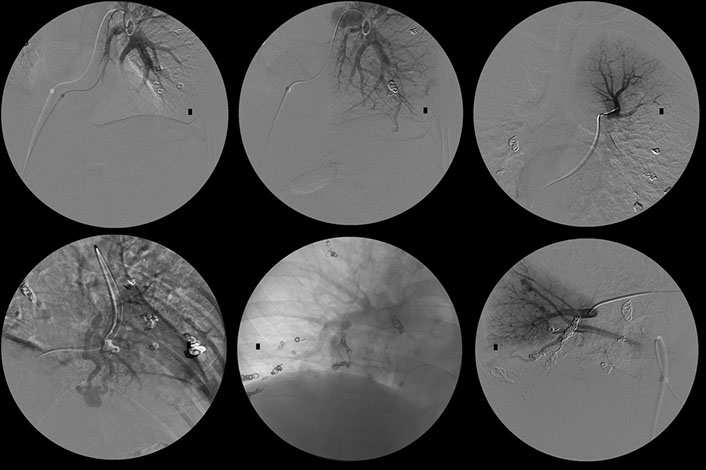

Control of bleeding by embolization.

Bleeding from a pelvic vessel resulting from a fracture, controlled by embolisation